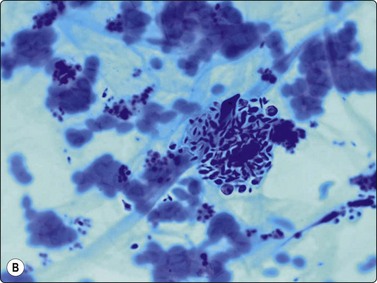

image image

Fig. 18.7 (A) Cohesive rounded sarcoid granuloma with occasional lymphocytes (Giemsa,

×400); (B) Rounded sarcoid granuloma (Pap, ×400).